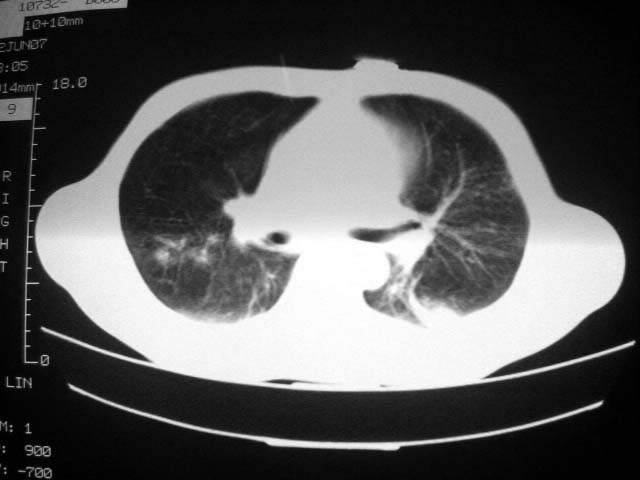

患者现无咳嗽咳痰及咳血,肝功好转,血清白蛋白降低,球蛋白升高,白球比小于0.5.少量腹水。

患者近期复查胸ct正常,轻度肝功异常,保肝、抗病毒(拉美夫叮)治疗中。